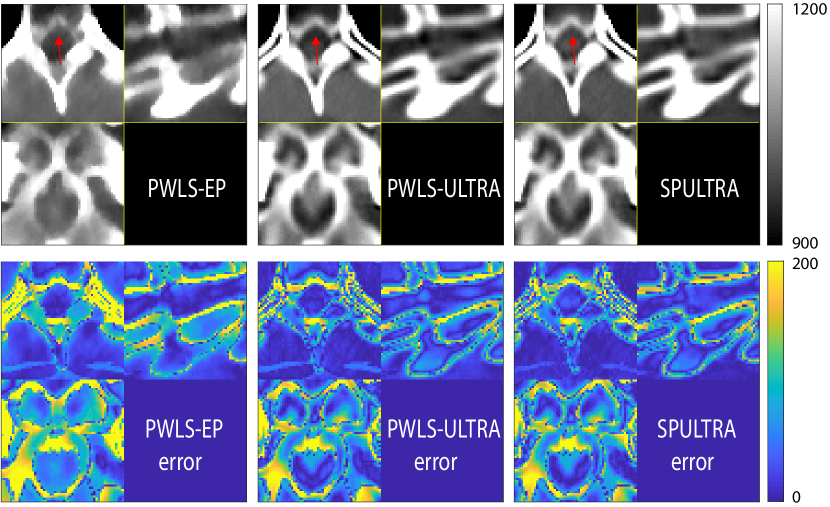

Fig. 4 shows the reconstructed images and the corresponding error images for PWLS-EP, PWLS-ULTRA, and SPULTRA, at and . Compared to the PWLS-EP result, both PWLS-ULTRA and SPULTRA achieved significant improvements in image quality in terms of sharper reconstructions of anatomical structures such as bones and soft tissues, and suppressing the noise. However, the PWLS-ULTRA method introduces bias in the reconstructions, which leads to larger reconstruction errors compared to the proposed SPULTRA method. In Fig. 4, we marked three 3D ROIs in the axial plane, i.e., ROI 1, ROI 2, and ROI 3. Fig. 5 shows the zoom-in images of a 3D plot of ROI 1, and those of ROI 2 and ROI 3 are shown in the supplement. We also plot the evolution of RMSE through the axial slices of the three 3D ROIs in Fig. 6. The figures demonstrate that SPULTRA clearly outperforms the competing PWLS-EP and PWLS-ULTRA schemes.

The above advantages of SPULTRA can be seen more clearly when observing the image profiles. Fig. 7 plots the image profiles for the three methods together with that of the ground-truth image. Fig. 4 shows the horizontal green solid line and the vertical red dashed line, whose intensities are plotted in Fig. 7. It is obvious that the profiles for SPULTRA are closest to the ground-truth among the three compared methods. The gap between the profiles of the PWLS-based methods and the ground-truth shows the bias caused by the compared PWLS methods.

Fig. 14 and Fig. 15 plot the zoom-ins and the corresponding error images of ROI 2 and ROI 3 for the XCAT phantom simulations in Section V.A, with and , respectively. In Fig. 15, we highlighted a region in the axial slice with small red arrows. We show the zoom-ins of the ground-truth ROI 2 and ROI 3 of the XCAT phantom in Fig. 16. The results show that SPULTRA improves image quality over PWLS-EP and PWLS-ULTRA by reducing bias and improving image edges.